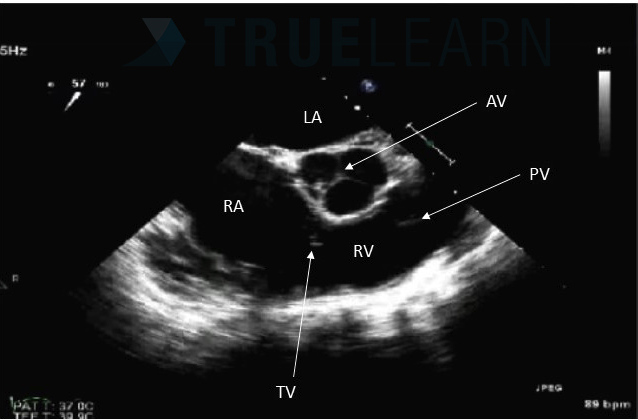

Arrow is Pointing at What Structure?

What is this view?